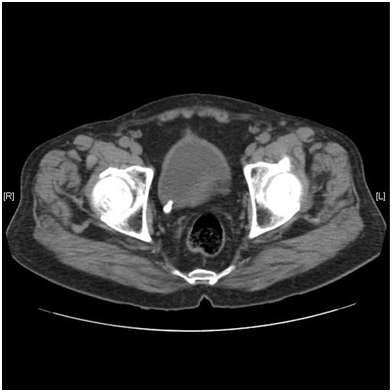

A 70year male presented to us with complaints of dysuria. There was no history of flank pain. He was a known asthmatic and had undergone transurethral resection of prostate 7years back. Physical examination was unremarkable. Urinalysis showed >100 pus cells per high power field. Urine was sent for culture. Routine biochemical parameters were normal. Ultrasonography showed a calculus at the right ureterovesical junction. An unenhanced helical CT scan was done which showed a right ureterovesical calculus of size 10mm and density 450HU (Figure 1). There was no hydronephrosis, hydroureter, perinephric or periureteral stranding. The CT was repeated in the prone position to differentiate whether it was calculus at the ureterovesical junction or if it was calculus in the bladder lying near the ureterovesical junction. The prone scan showed no change in the position of the calculus (Figure 2), which led to the conclusion that it was an ureterovesical junction calculus. Ureterorenoscopy was planned. However, on cystoscopy it was found that the calculus was not at the ureterovesical junction but was in a paraureteral diverticulum having a narrow mouth. It was dealt with by fragmentation using pneumatic lithotripsy and then removing the fragments.

Figure 1 Unenhanced Helical CT scan in supine position showing the calculus.